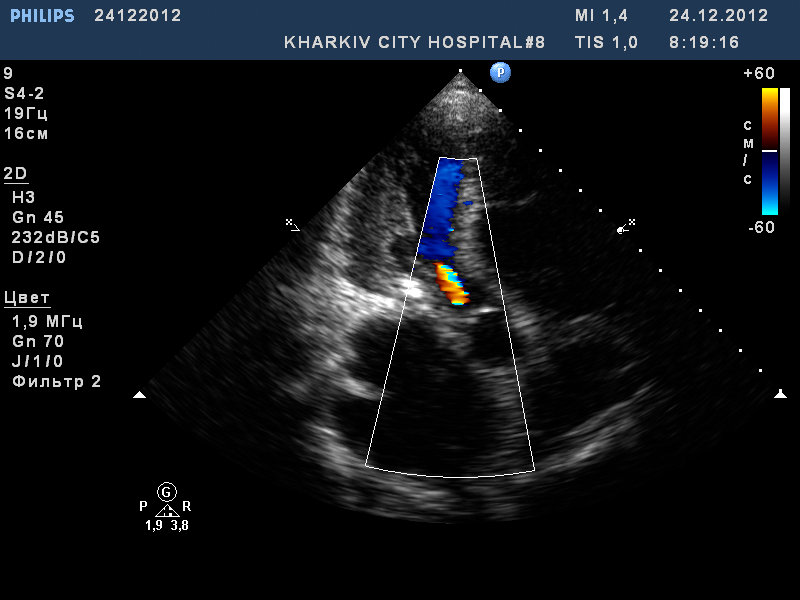

Пациент 52 лет. Поступил с нарушение ритма.

Заключение узи : склеротические изменения аорты, фиброзные изменения створок аортального клапана, незначительная недостаточность аортального клапана, частичный отрыв хорд передней створки митрального клапана, значительный митральный стеноз, умеренная МН, дилатация левого предсердия (6,0см), гипертрофия левого желудочка.

1.jpg